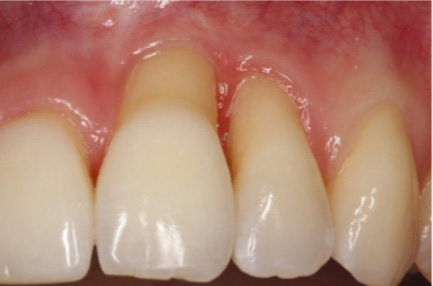

4、牙龈退缩:牙龈退缩后牙骨质暴露并易磨损,可导致牙本质进一步暴露。先天性解剖结构缺陷、根面菌斑堆积、牙周病以及牙周病的不当治疗、正畸治疗、增龄性因素等均与牙龈退缩密切相关。